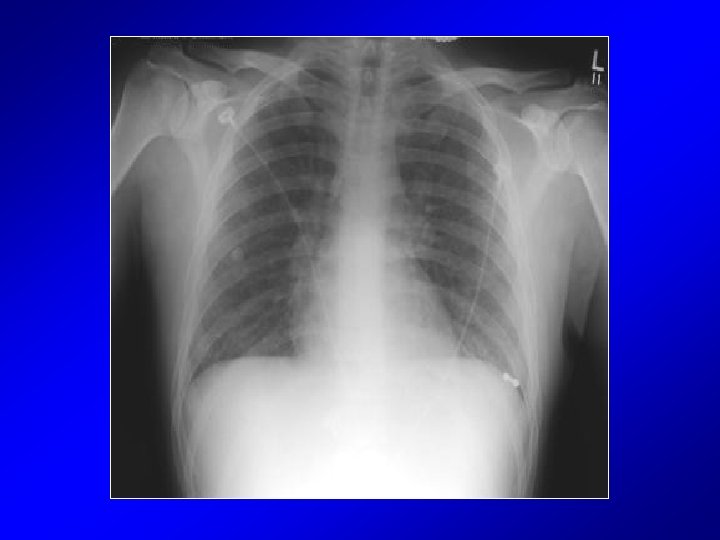

Clinical Course • Admitted to ICU – Intravenous furosemide – Supplemental oxygen • 36 hours after admission – Dyspnea resolved – Lungs clear on exam – Chest x-ray improved – O 2 saturation – 96% on room air – Patient offered substance counseling but declined and was discharged home